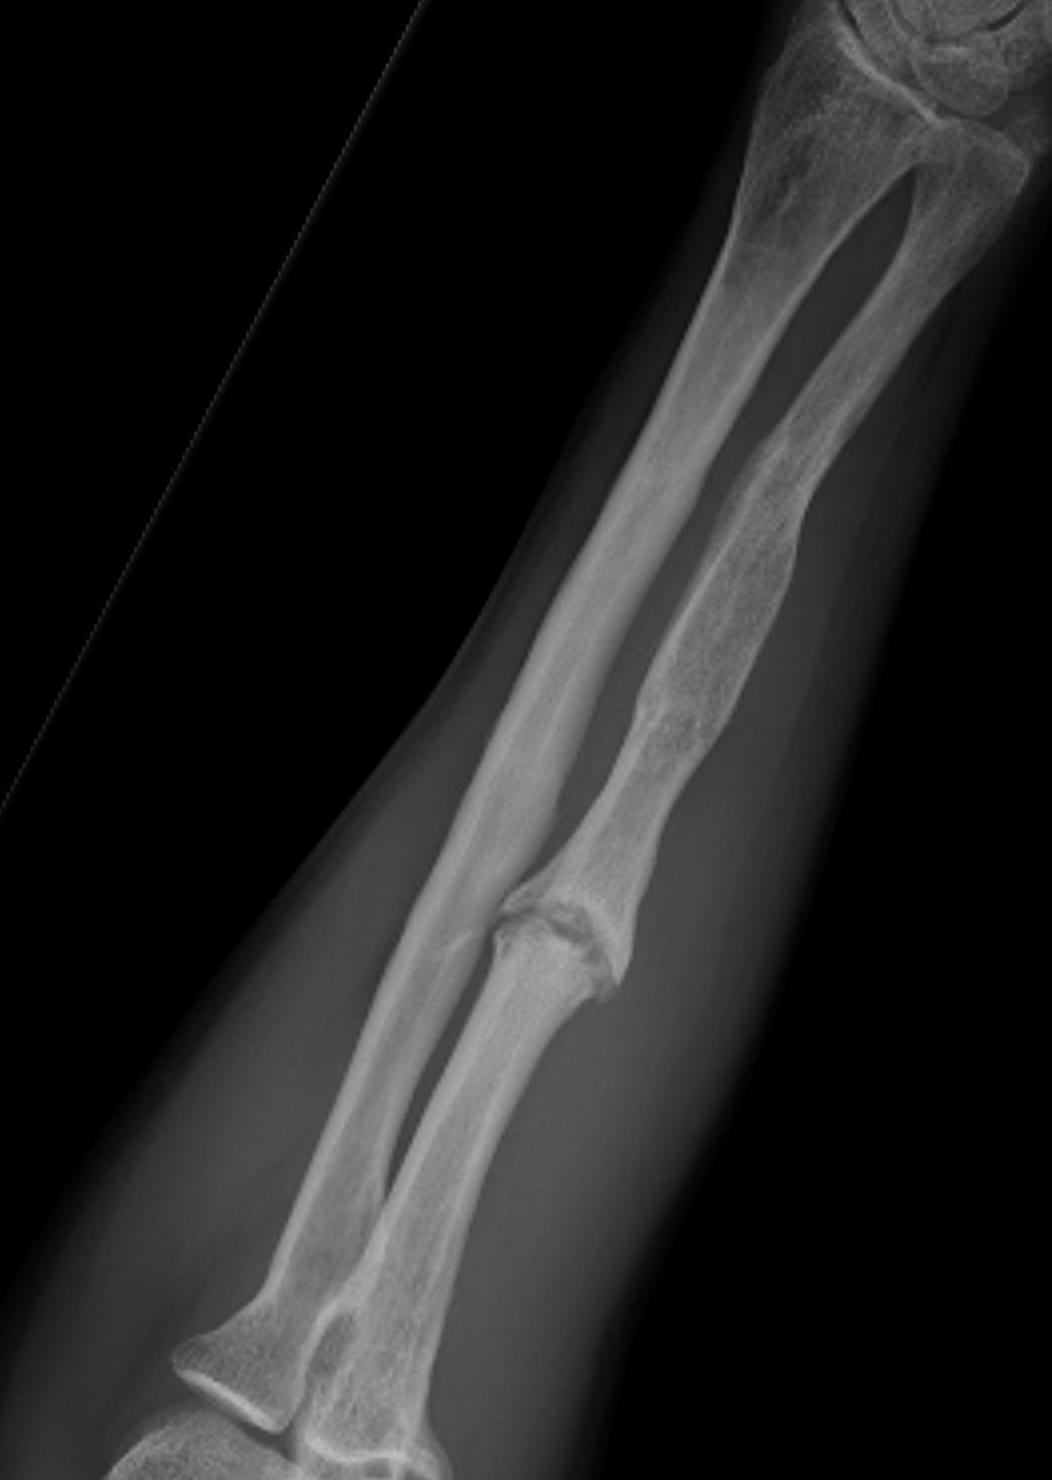

Night stick injury - direct blow or trauma to ulna

Distal 1/3

Midshaft / middle 1/3

Proximal - beware Monteggia / radial head dislocation

Distal 1/3 Middle 1/3 Proximal 1/3